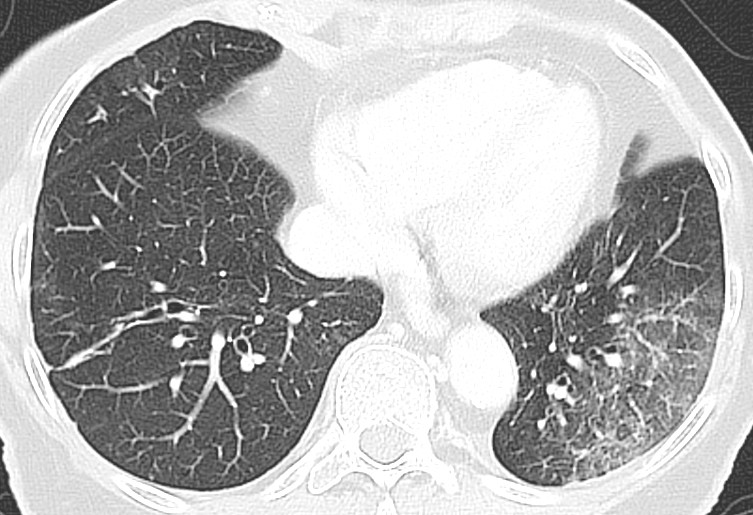

Typical CT findings vary with symptom duration and can be divided into three stages: an early phase, an intermediate phase that extends from 3–5 days after symptom onset, and a late phase.

There are not always CT findings the first few days after symptom onset. In a material with symptomatic, but unspecified patients, 56 % had normal CT findings within two days of symptom onset (12), declining to 9 % 3–5 days after symptom onset and 4 % 6–12 days after symptom onset. The frequency of findings varies with the severity of the disease. Initial diagnostic imaging yielded normal findings for 18 % in a cohort of patients who were not severely ill, but in only 3 % of patients who were (15). Typical CT findings are multiple, bilateral ground-glass opacities with peripheral distribution, most frequently located in the lower lobes. In the intermediate phase there are increasing amounts of consolidation and affection of several lobes, and increased septation with crazy paving as sign of interstitial affection. In the late phase there is increasing total extension, but ground-glass opacities and consolidation are still the dominant findings (12, 16). Figures 4, 5 and 6 show typical CT findings in different phases of COVID-19.

In a severe disease course, distortion of the lung architecture, traction bronchiectasis, enlarged lymph nodes and pleural fluid can be detected. These are findings that are not specific for COVID-19 (17).

The sensitivity of the examination in detecting COVID-19 pneumonias is reported as being up to 97 % (18, 19), and it may therefore be more sensitive than PCR of specimens from the upper respiratory tract (18, 20, 21). There is evidence that the viral load is significantly higher in the lower than in the upper respiratory tract in COVID-19 pneumonia (8, 9). Detection of SARS-CoV-2 in cases of pneumonia should therefore include specimens from the lower respiratory tract (8). CT changes were included as an important diagnostic feature (major evidence) in Hubei after 12 February 2020 (22). Reports of CT findings prior to the onset of clinical symptoms (23) proposed to use CT as a screening tool – together with PCR – for potentially infectious patients where false negative PCR tests are suspected (24). Where there is a low pre-test probability of disease, however, CT has a low positive predictive value (25), and leading communities in Europe and the USA have warned against using CT as a screening tool (2, 4, 26). The time elapsing from symptom onset to CT findings varies as well, which means that a normal CT shortly after symptom onset does not rule out COVID-19.

The pulmonary changes with COVID-19 are non-specific and overlap with findings for other acute interstitial pneumonias, including influenza (27, 28). As incidental findings on CT scans carried out on other indications, the changes should nonetheless lead to prompt COVID-19 testing during an ongoing pandemic.